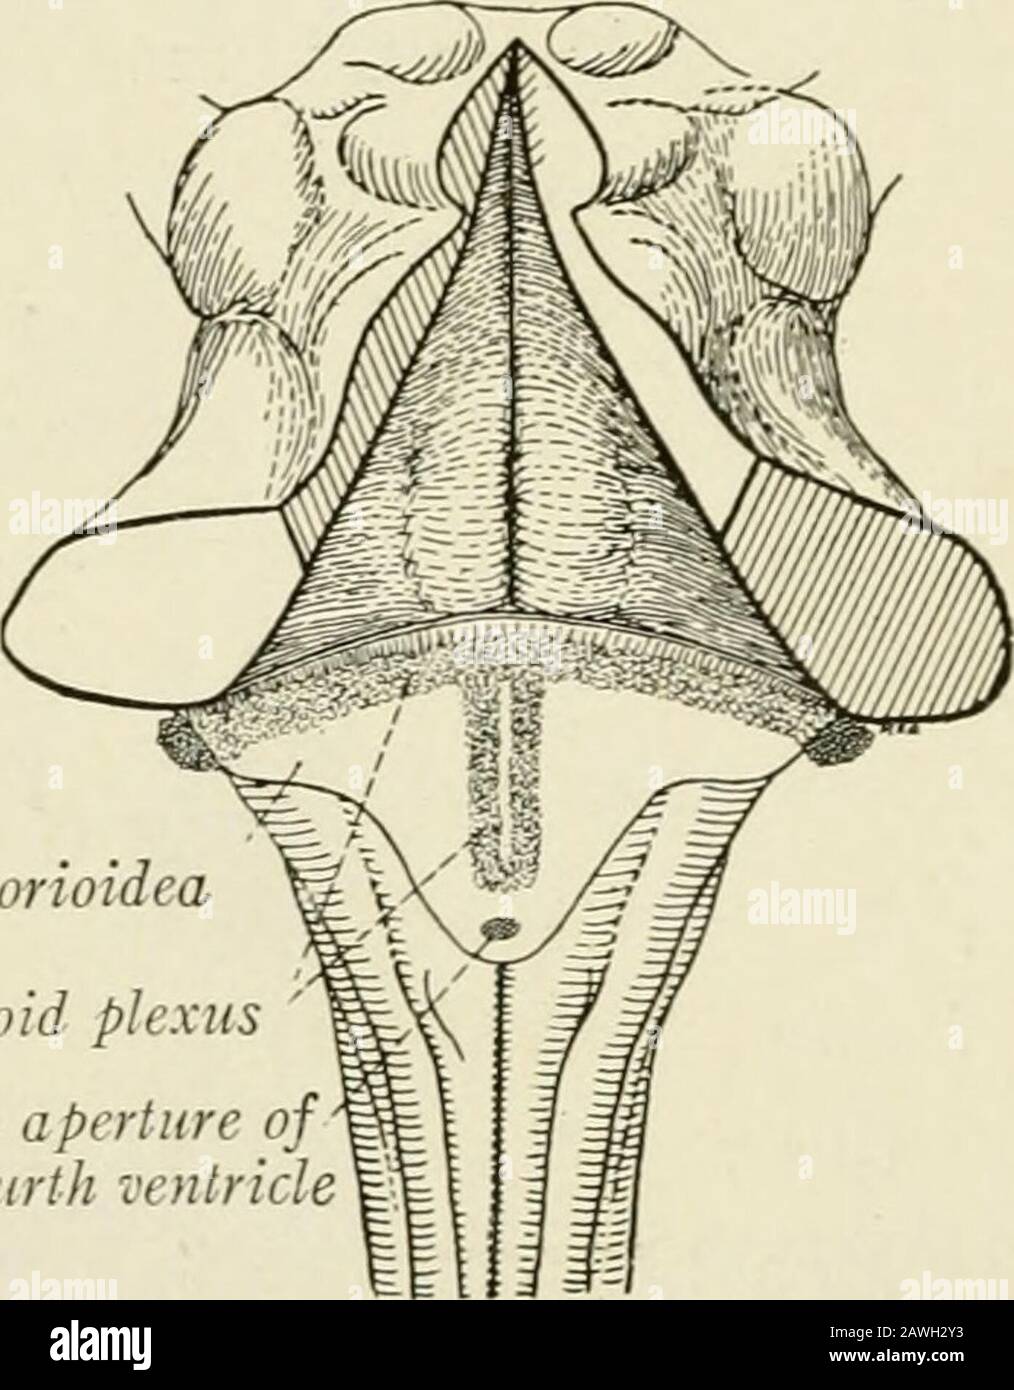

RM2AWH2Y3–Die Anatomie des Nervensystems, vom Standpunkt der Entwicklung und Funktion. Die Fasern des Nervus facialis Bendum den Zellkern der Entführten. Der Locus 121, DER AUS pigmentednerven Nervenzellen besteht, erstreckt sich von der Fovea Superior bis zur Thecerebral Aquädukt ist eine flache, meist blassblaue Nut, darunter liegt die substantia ferruginea. Beginnend mit dem zerebralen Aquädukt und durch das superiorale und das inferiore Fovea? Ist eine sehr wichtige Nut, der Sulcus limitans, der die Trennlinie zwischen den von t abgeleiteten Teilen wieder aufsaugt

RMRDJK4N–. Praktische Anatomie der Kaninchen: Eine elementare Labor Lehrbuch in Säugerzellen Anatomie. Kaninchen; Anatomie, Vergleichende. Das zentrale Nervensystem. 279 verbunden mit den zerebralen Aquädukt vorwärts und rückwärts mit dem zentralen Kanal. das Rückenmark. Sein Dach ist hauptsächlich von der anterioren und posterioren medulläre Vela gebildet, die - das Kleinhirn zu nahe beieinander angebracht werden, so dass sie zugrunde liegen. (B) Die rautenförmigen Schädelgrube (Fossa rhomboidea) ist die flachen Depression, die durch die Dicke der seitlichen und vorderen, die Wände und der Boden des Ventrikels eingeschlossen. Die mittlere Zeile zeigt ein narro

RMRENR10–. Praktische Anatomie der Hase [microform]: Eine elementare Labor Lehrbuch in Säugerzellen Anatomie. Lapins; Anatomie, Vergleichende; Kaninchen; Kaninchen; Lapins; Anatomie comparée. Die Centrai. Nekvous Svstem. iqj (a) Der vierte venWcle (ventriculus Quartus) ist die umfangreiche o^ ardstifh Th*" "-e rhombence' phalon / Es ist â"¢ eg: d orwards mit den zerebralen Aquädukt und Rückwärts mit pnncipal y von der anterioren und posterioren medulläre Vela Â" "ratXrd: s i°' "^"^'^'^^""""">" - - - - e-(b) Die rautenförmigen Schädelgrube (Fossa rhomboidea) ist die flache